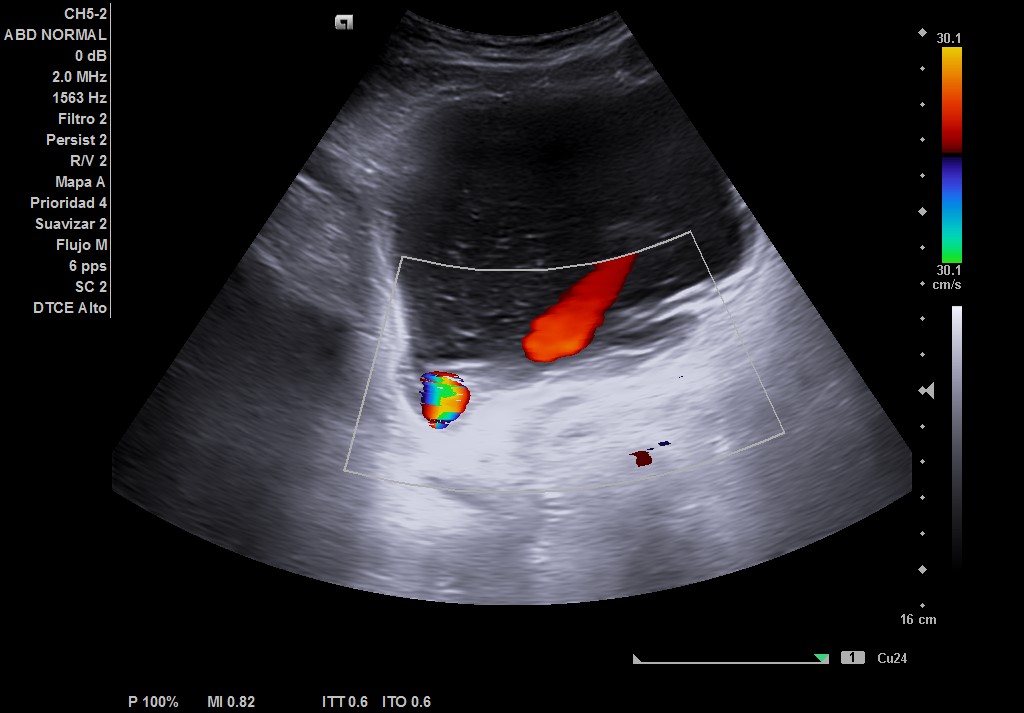

Ecografía tras ingerir 1 litro de agua y sin orinar posteriormente, con sonda convex: se visualiza vejiga repleccionada hasta 2 cm del ombligo, con > 550 cc (difícil de cuantificar por gran tamaño). Residuo postmiccional 525 cc, paredes de vejiga con signos de lucha, divertículo e imagen de «centelleo» en desembocadura de uréter derecho, pero sin afección del jet ureteral ipsilateral. Próstata de 67 cc aproximadamente, que protruye en vejiga. Riñones con ecoestructural normal sin dilatación en vía excretora.